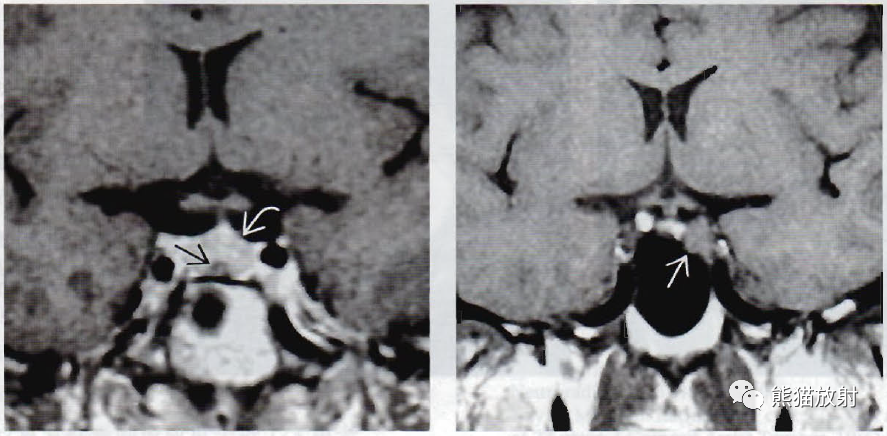

(左)冠状位图显示小的微腺瘤(箭)使右侧垂体轻度扩大,漏斗左移。

(右)冠状位显微病理学显示正常垂体包绕一小的无功能微腺瘤,为尸检偶然发现。

(左) 冠状位T1WI C+MR显示轻度扩大的垂体内有一强化稍弱的病灶。患者无症状,该病灶为偶然发现。垂体“偶发瘤”常见(见于15%~20%的病例) ,可能代表无功能性腺瘤或非肿瘤性囊肿(如中间部囊肿或Rathke裂囊肿) 。

(右) 一例催乳素升高的女性患者,冠状位T1WI MR显示垂体左侧部内一8mm的结节。多数微腺瘤位于侧方。